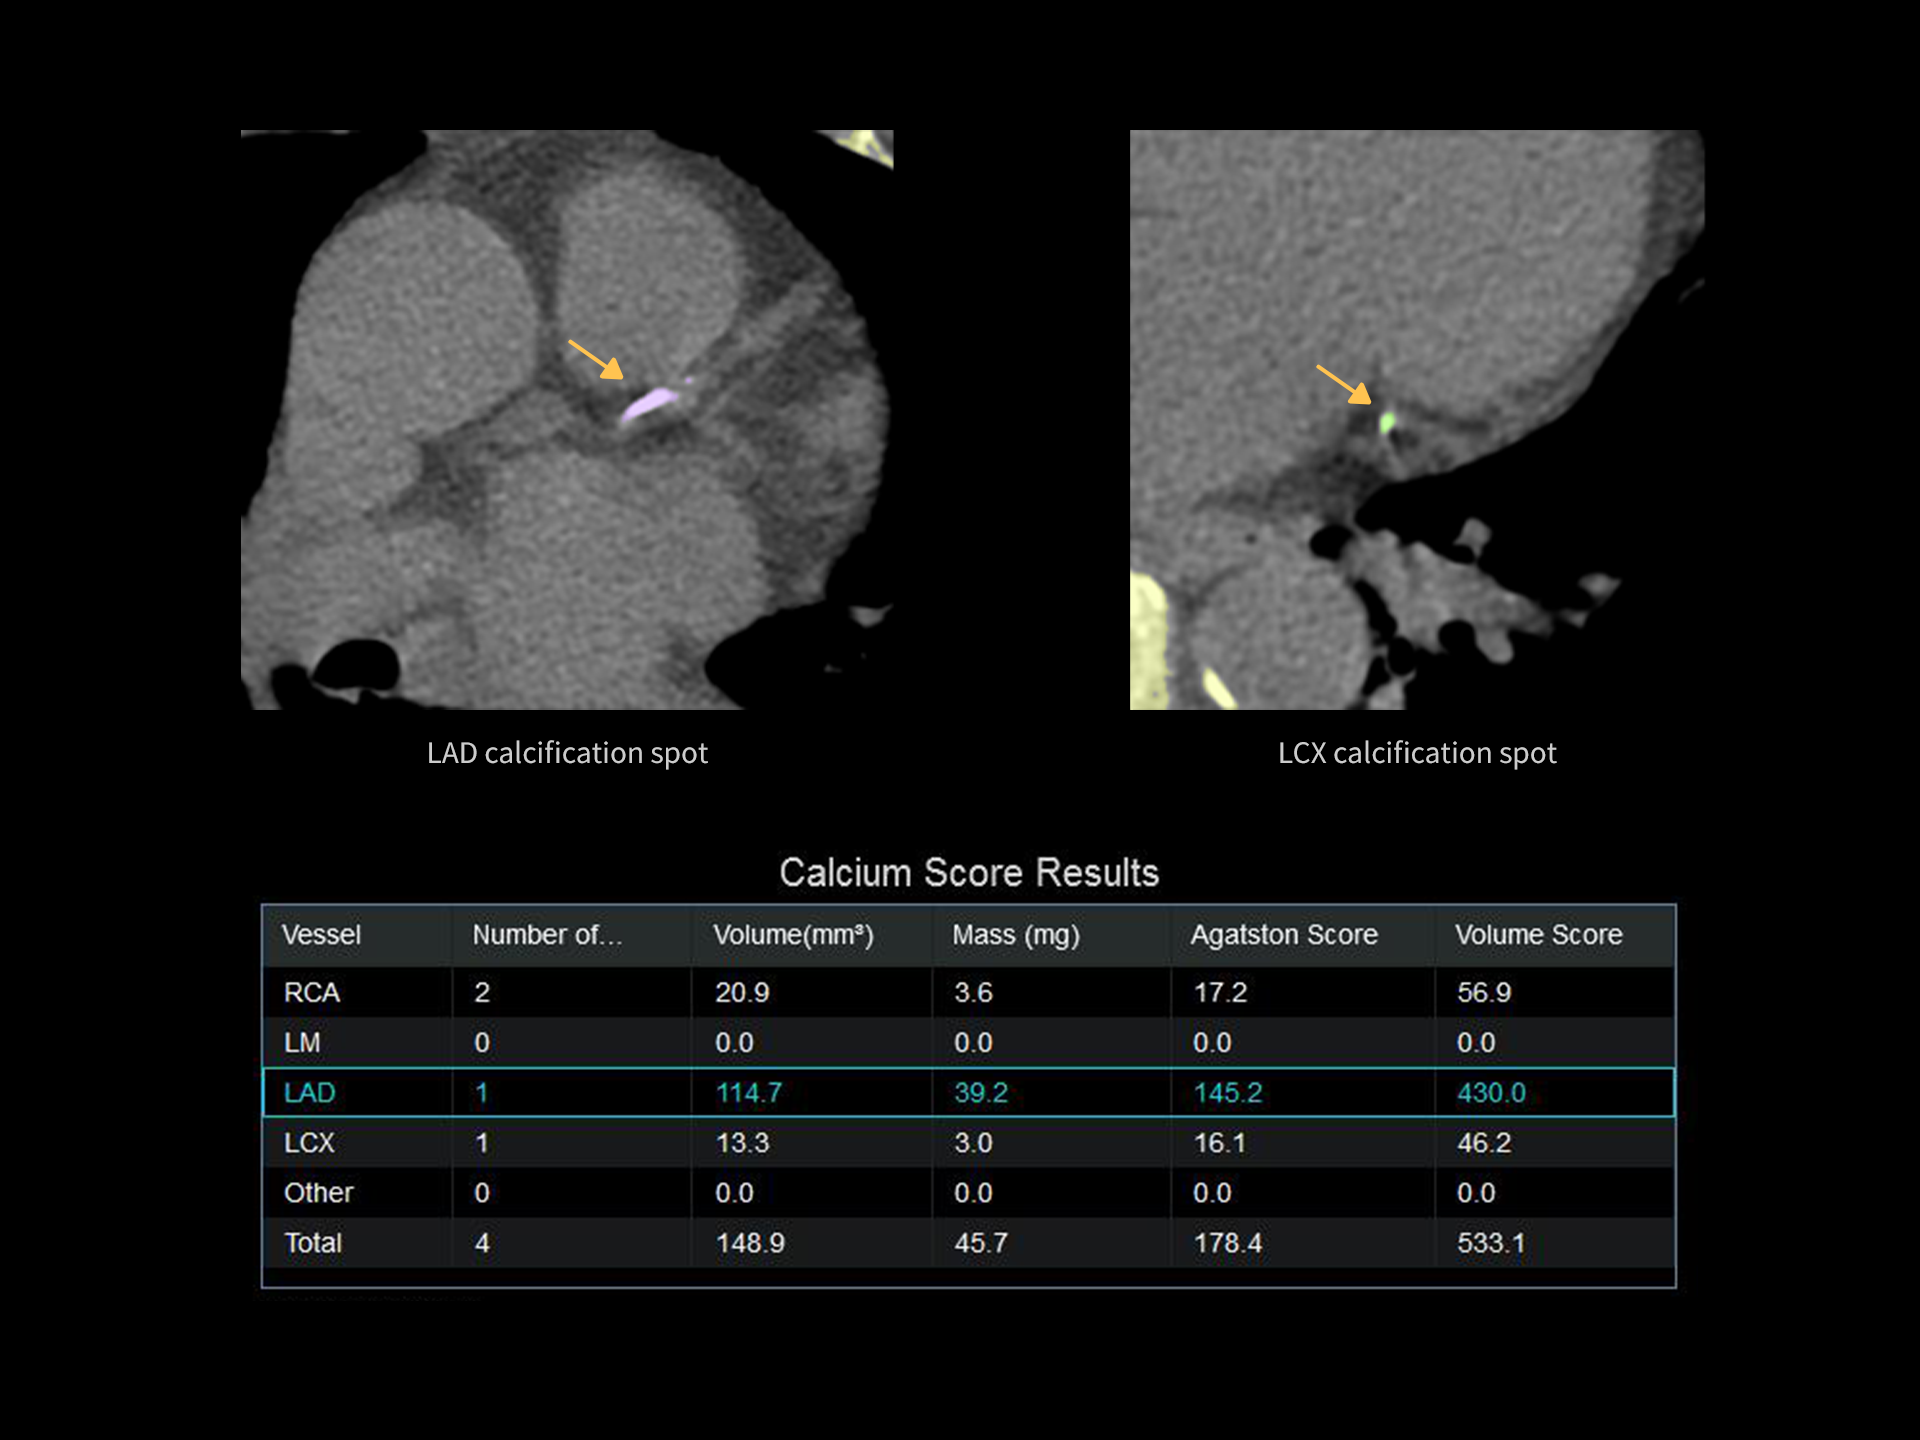

uCT Orion Elite deblochează noi posibilități în practica medicală. Sistemul suportă evaluarea scorului de calciu coronarian cu sincronizare ECG* pentru depistarea precoce a bolilor cardiovasculare și permite scanări dual-energy* pentru vizualizarea și analiza compozițională a tofilor gutoși.